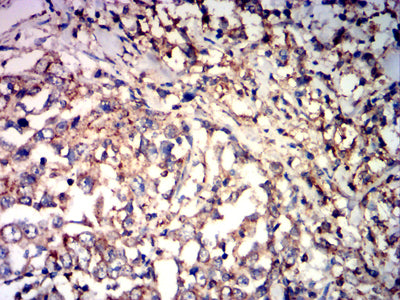

Immunohistochemical analysis of paraffin-embedded human stomach cancer tissues using CD85K mouse mAb with DAB staining.